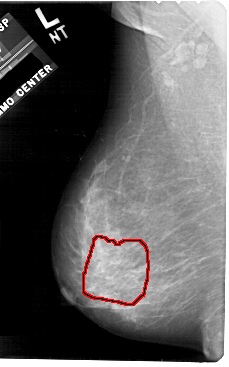

A_1906_1.LEFT_CC

LEFT_CC LINES 5491 PIXELS_PER_LINE 3196 BITS_PER_PIXEL 12 RESOLUTION 43.5 OVERLAY

FILE: A_1906_1.LEFT_CC.OVERLAY

TOTAL_ABNORMALITIES 1

ABNORMALITY 1

LESION_TYPE CALCIFICATION TYPE PLEOMORPHIC DISTRIBUTION SEGMENTAL

ASSESSMENT 4

SUBTLETY 3

PATHOLOGY MALIGNANT

TOTAL_OUTLINES 1

BOUNDARY